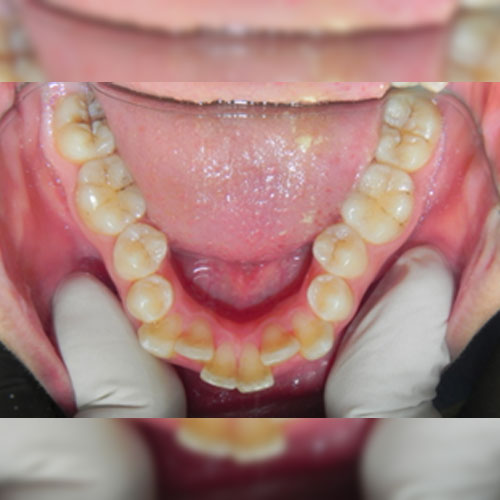

Smile Transformations

Real Patient Smile Transformations